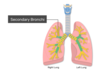

Label the diagram

Label this diagram

Label the diagram

Label this diagram

Label the diagram